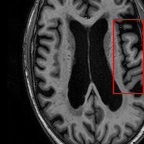

Sparsity LI 2D CNN 3D CNN Ours GT

4 Refer to caption (a) 0.6787/0.7972 Refer to caption (b) 0.8143/0.8776 Refer to caption (c) 0.8190/0.8714 Refer to caption (d) 0.8664/0.9085 Refer to caption (e) GM/WM

Refer to caption (f) 0.6808/0.7161 Refer to caption (g) 0.8103/0.8631 Refer to caption (h) 0.7950/0.8606 Refer to caption (i) 0.8598/0.9115 Refer to caption (j) GM/WM

Figure 6: Visual comparison of gray matter (Green)/white matter (Blue) segmentation over different methods, with respective DICE scores listed under the images.

In Fig. 6, we demonstrate the advantage of the proposed method in brain matter segmentation. It is clear that although 2D and 3D CNN generates visually plausible interpolation as presented in Fig. 5, the brain matters are easily misclassified due to incorrect anatomical structures and blurred details.